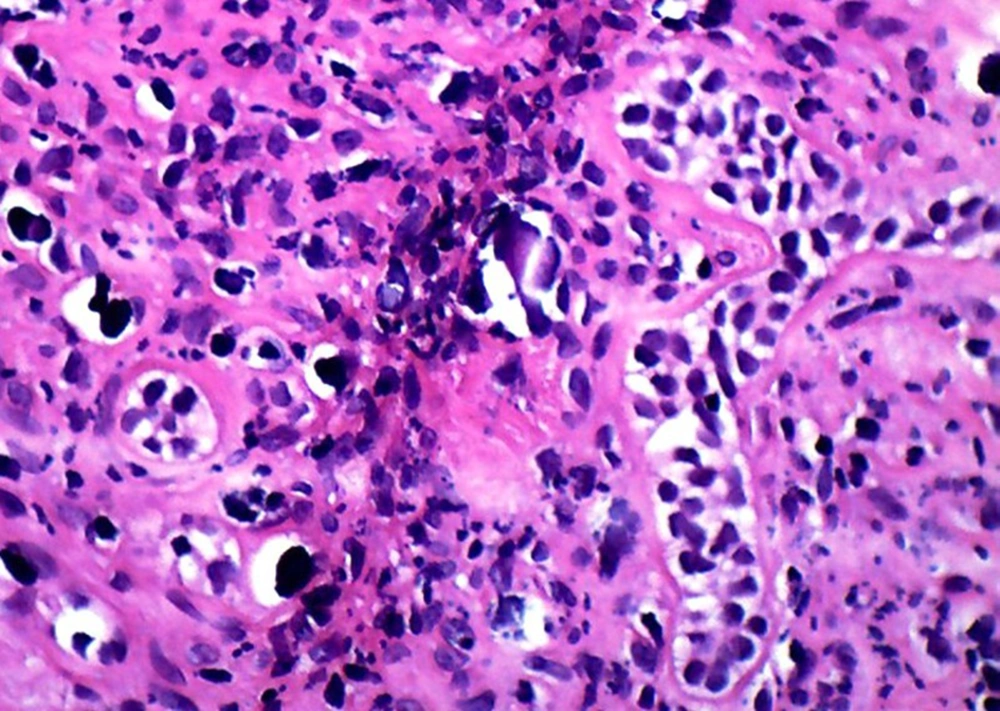

A 13-year-old boy with the chief complaint of multiple unerupted teeth was referred to department of Oral and Maxillofacial Surgery of Ahvaz University of Medical Sciences in May 2013. The panoramic radiograph revealed 15 unerupted teeth (8 in mandible and 7 in maxilla) with large pericoronal radiolucent zone (enlarged follicles) delineated by a well-defined sclerotic borders (Figure 1). Tooth abnormalities such as amelogenesis imperfecta were not seen. Medical and familial history was unremarkable and his siblings had normal dentition. The patient had normal intelligence. He did not have other signs and symptoms like cleidocranial dysplasia, Gardner syndrome, or mucopolysaccharidosis (three syndromes with tendency to multiple impactions). The incisional biopsy was performed with provisional diagnosis of Gorlin syndrome (multiple keratocystic odontogenic tumors). Microscopic examination revealed a dense and cellular fibrous connective tissue with numerous deposits of calcifications. Collagen fibers were arranged in whorled structures. Cords and islands of odontogenic epithelium with numerous clear cells were surrounded by these deposits. Calcifications were found in the whorled areas. There were many small circular droplets of basophilic calcified material resembling cementum. Most of the droplets were homogenous (up to 95%), but some revealed concentric layering similar to Liesegang rings of Pindborg tumor. The diagnosis was atypical follicles with odontogenic fibroma-like changes (WHO type) or hyperplastic calcified dental follicles (Figures 2- 4). Then, the excisional biopsy was performed for mandibular lesions. Grossly, the specimen consisted of multiple pieces of creamy brown soft tissues surrounding the crown of multiple extracted teeth totally measuring 5 × 5 × 1 cm. The lesions showed fine surface nodularities and produced a distinct grating sound during sectioning (Figure 5). The initial diagnosis has been confirmed. Additional surgical procedure must be performed for maxillary lesion in future.